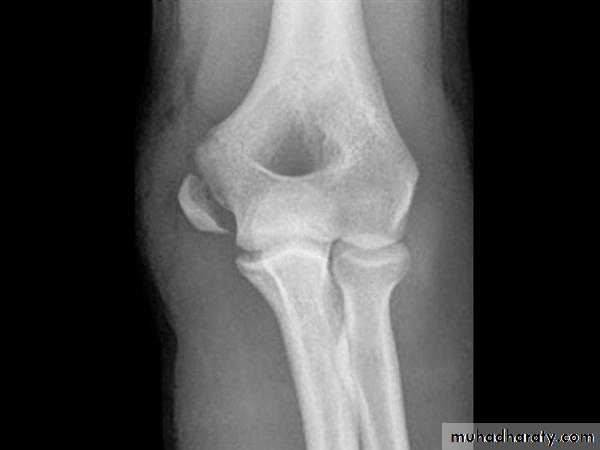

Medial Epicondyle Fracture

Represents 5-10 percent of pediatric elbow fractures.Occurs with valgus stress to the elbow, which avulses the medial epicondyle.

Frequently associated with an elbow dislocation

C.F.:

Pain.swelling on the medial side.

Sensation in the ulna fingers should be tested.

Due to the extreme, the avulsed fragment may become entrapped in the joint even when there is no dislocation of the elbow.

Classification and Treatment

Nondisplaced and minimally displaced (less than 5 mm of displacement)- May be treated without fixation, and early motion to avoid stiffness.

Displaced more than 5 mm -ORIF.

Only absolute indication is entrapped fragment after dislocation with incongruent elbow joint.